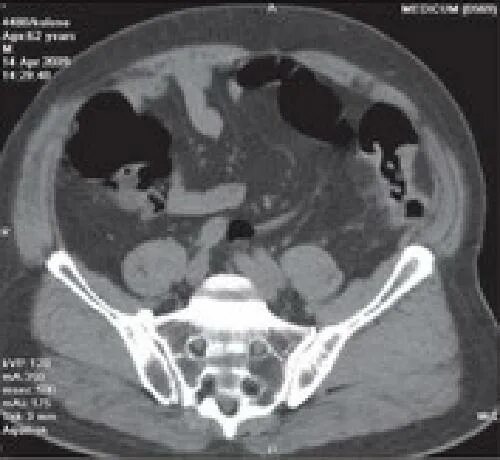

Обследование кт кишечника